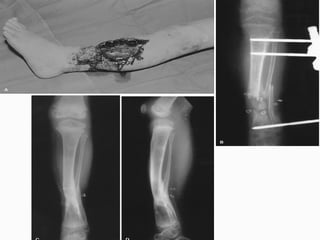

FRACTURA EXPUESTA Es la perdida de continuidad ósea, en  la que el foco de fractura se pone en contacto con el medio ambiente

PARAMETROS DE CLASIFICACION Medio ambiente en que sucedió Tiempo transcurrido entre la lesión y el tratamiento hospitalario El grado de lesión de las partes blandas del miembro afectado o áreas circunvecinas

CLASIFICACION DE LAS FRACTURAS EXPUESTAS Contaminadas : < de 6 hrs de evolución, contaminación por gérmenes del medio ambiente o el agente agresor Infectadas : > de 6 hrs de evolución, reproducción de los gérmenes localmente Complicadas : es la que se acompaña de lesiones en órganos, sistemas, o elementos anatómicos vecinos

CLASIFICACION Las clasificaciones complementarias se basan en el grado de lesión de partes blandas, siendo la mas utilizada la de Gustilo

CLASIFICACION DE GUSTILLO I:  Herida < 1 cm. Herida limpia realizada por un fragmento puntiagudo de hueso que perfora la piel, existe escasa lesión a tejidos blandos, sin signos de aplastamiento, son por baja energía

CLASIFICACION DE GUSTILLO II:  Longitud > 1 cm. Sin colgajos, avulsiones y sin una gran lesión de tejido blando, existe un mínimo a moderado aplastamiento, conminución y contaminación moderada

CLASIFICACION DE GUSTILLO III:  Lesión extensa de tejidos blandos que afectan al músculo, piel y estructuras neurovasculares, suele existir un alto grado de contaminación, son por alta energía A)  cobertura adecuada de tejido blando del hueso, sin importar el tamaño de la herida

CLASIFICACION DE GUSTILLO B)  Afectación extensa o perdida del tejido blando con exposición del hueso, contaminación masiva y una grave fractura conminuta C)  Se asocia a lesión arterial  que necesita reparación independientemente del grado de lesión del tejido blando